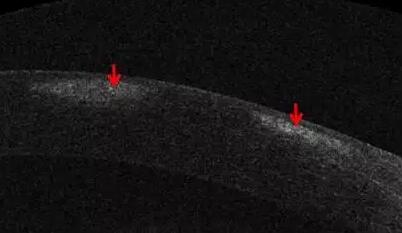

1、角膜分层观察 OCT 轴向分辨率高达5μm,远高于UBM(20--60μm),可识别出泪膜、上皮层、前弹力层、基质层、后弹力层/内皮层

2、角膜厚度评估,角膜水肿、瘢痕、混浊、溃疡、异物、炎症、胬肉等断层观察

3、角膜屈光手术后角膜瓣观察、角膜厚度评估等

4、后弹力层角膜内皮移植术(DSEK)、板层角膜移植术、白内障术后内皮层脱落等术后观察